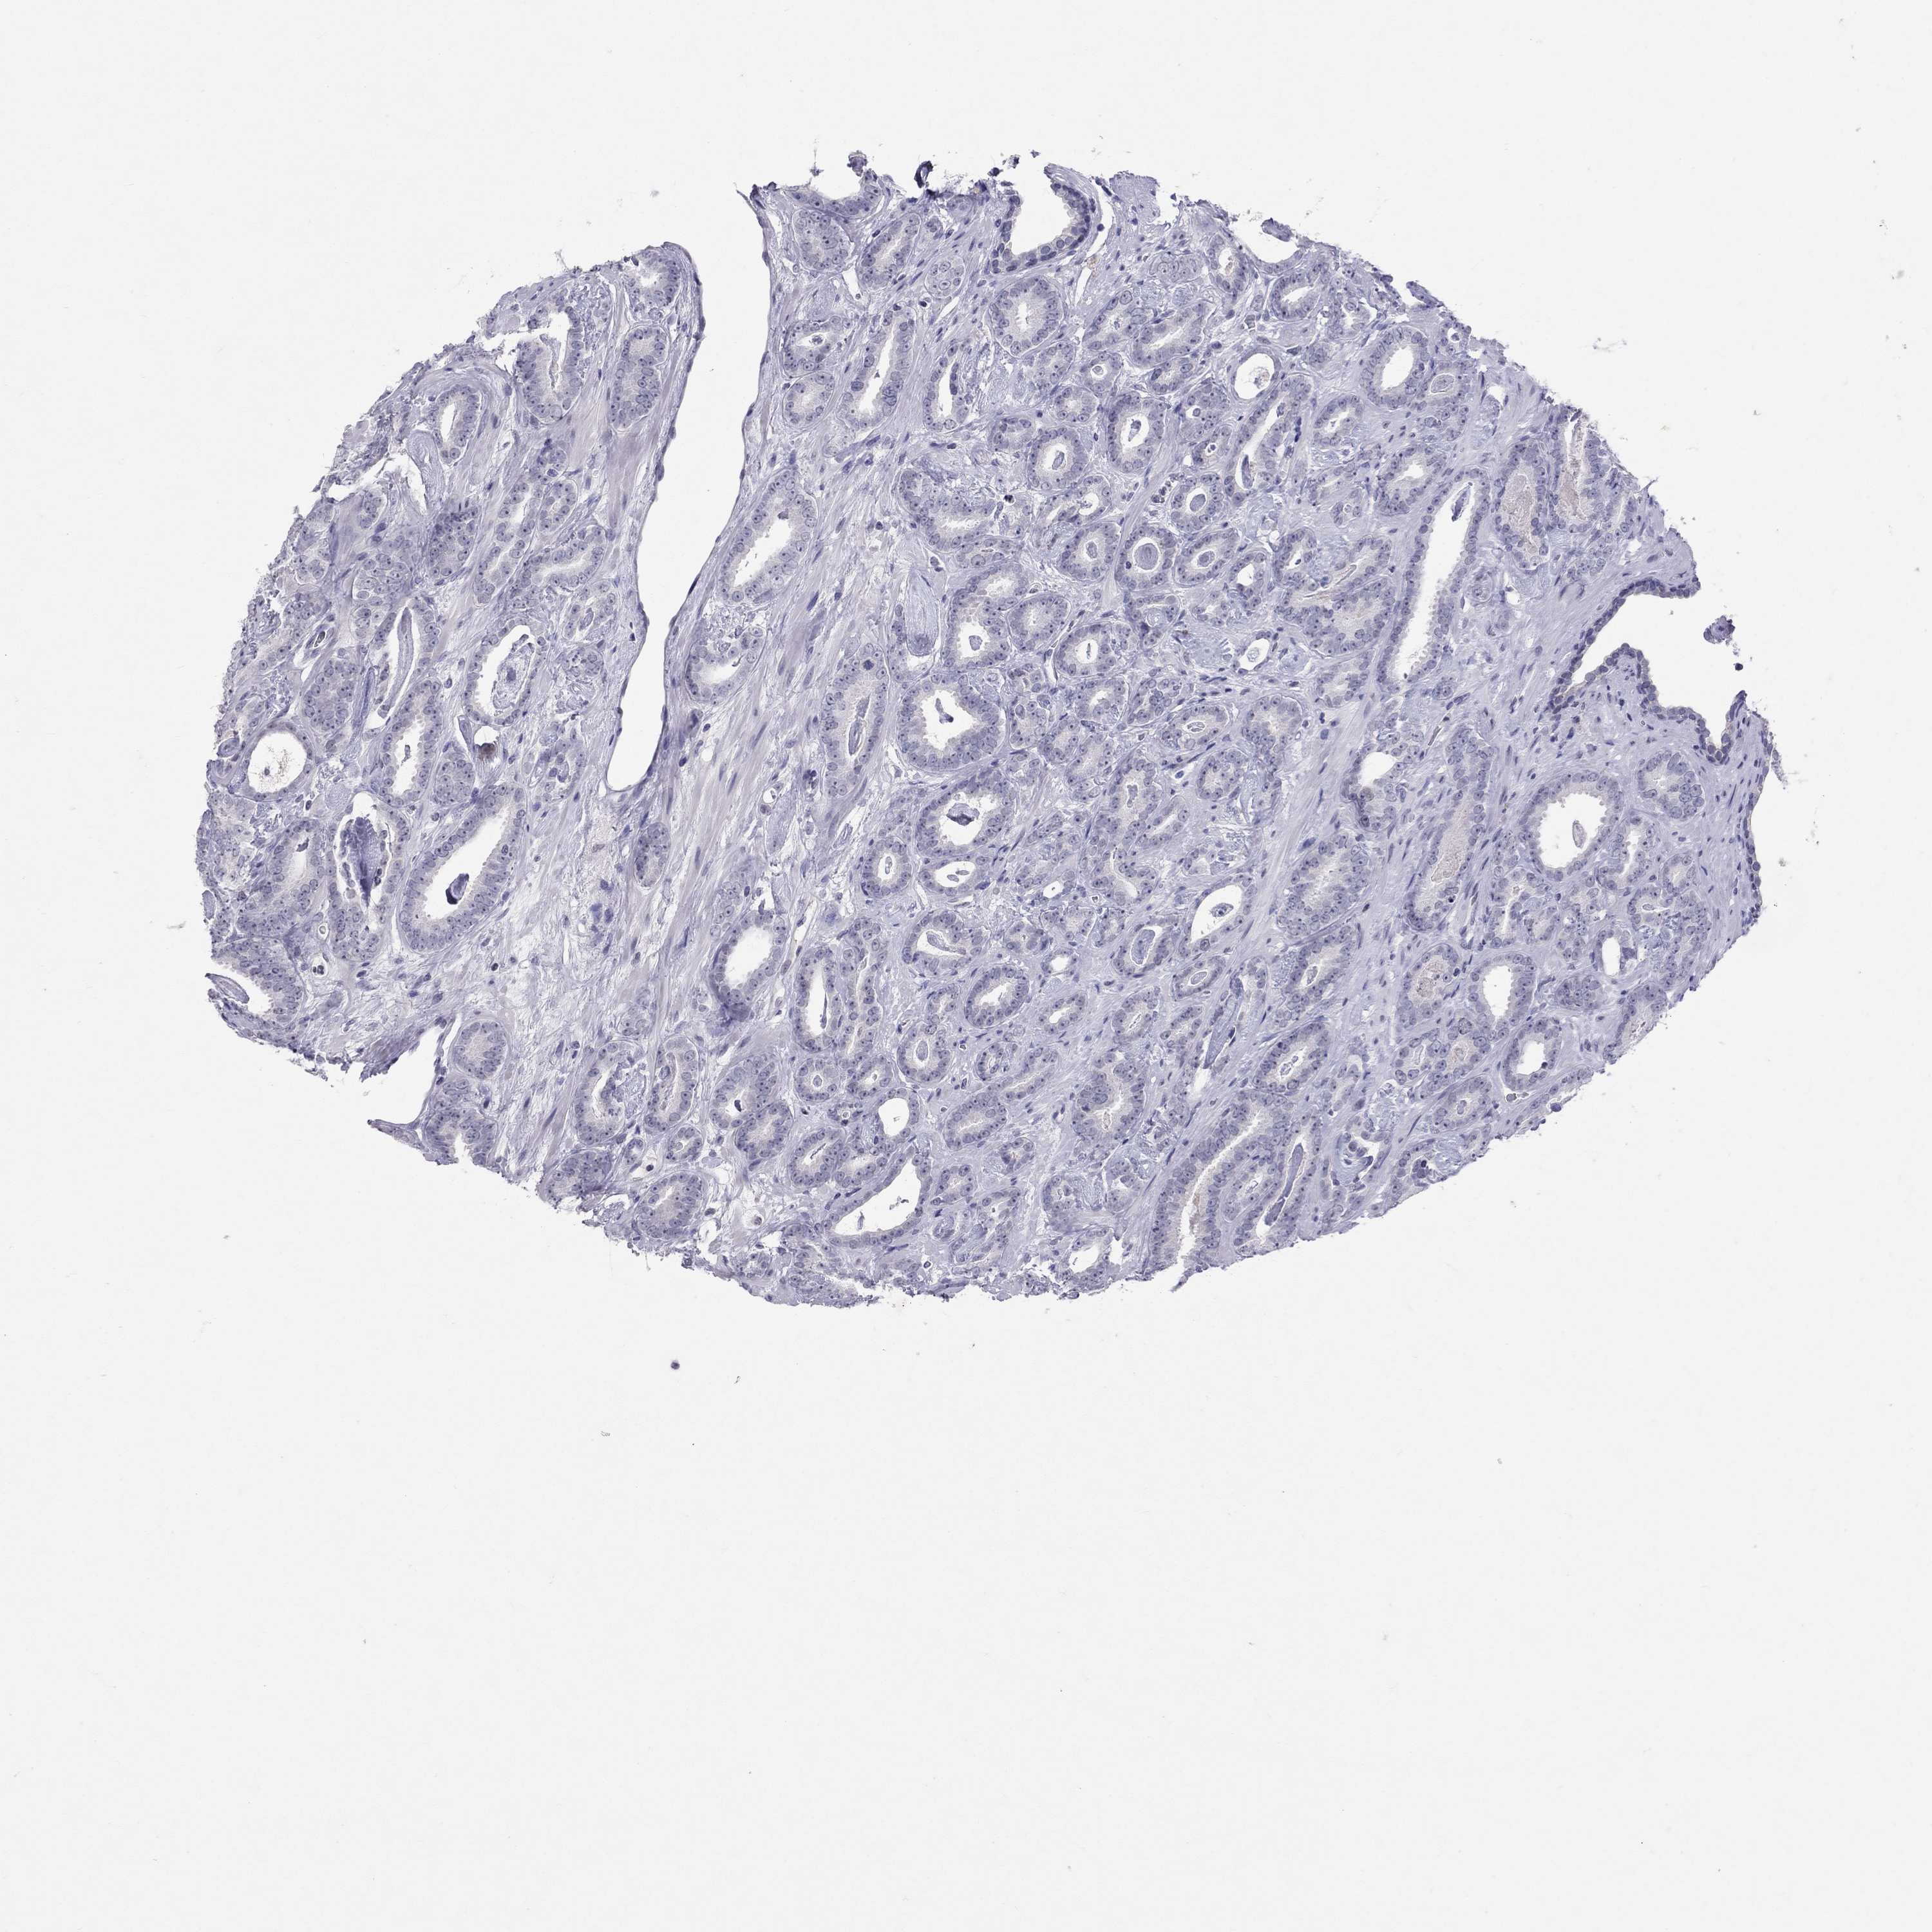

PROSTATE CANCER - Protein expressioni

A mouse-over function shows sample information and annotation data. Click on an image to view it in a full screen mode. Samples can be filtered based on level of antibody staining by selecting one or several of the following categories: high, medium, low and not detected. The assay and annotation is described here.

Note that samples used for immunohistochemistry by the Human Protein Atlas do not correspond to samples in the TCGA dataset.

Antibody stainingi

Antibody staining in the annotated cell types in the current human tissue is reported as not detected, low, medium, or high, based on conventional immunohistochemistry profiling in selected tissues. This score is based on the combination of the staining intensity and fraction of stained cells.

Each image is clickable and will lead to virtual microscopy that enables deeper exploration of all samples and also displays staining intensity scores, fraction scores and subcellular localization as well as patient and tissue information for each sample.

Antibody HPA077658

Antibody HPA077748

Staining

High

Medium

Low

Not detected

Intensity

Strong

Moderate

Weak

Negative

Quantity

>75%

75%-25%

<25%

None

Location

Nuclear

Cytoplasmic/membranous

Cytoplasmic/membranous,nuclear

Adenocarcinoma, Medium grade

Adenocarcinoma, High grade

Adenocarcinoma, NOS

Adenocarcinoma, Low grade